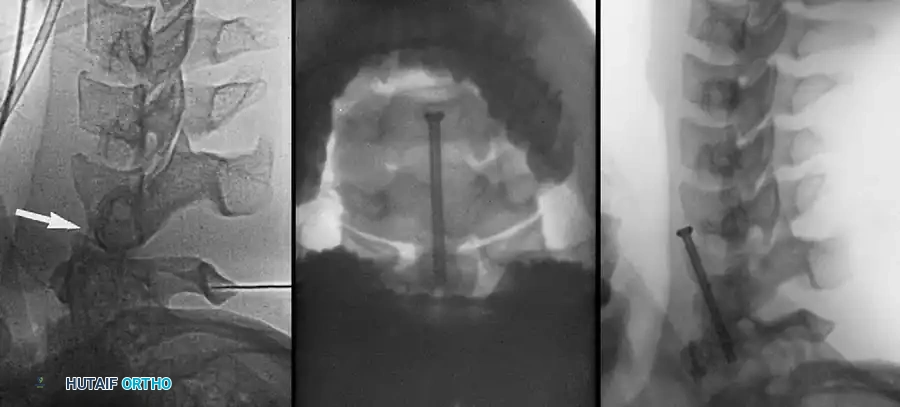

Closed Reduction via Skeletal Traction

After initial ATLS medical stabilization, spinal alignment is typically attempted via closed skeletal traction using spring-loaded Gardner-Wells tongs or a halo ring.

Traction Protocol:

* Apply an initial 10 lbs of weight to counteract the weight of the head.

* Add 5 lbs for each level of injury (e.g., a C5-C6 dislocation would require roughly 10 lbs + (5 levels × 5 lbs) = 35 lbs).

* Add weight in 5-lb increments with continuous clinical and radiographic monitoring.

* Maximum safe limits are generally considered to be 40 to 50 lbs, though some rigid dislocations may require more under strict fluoroscopic guidance.

Fig 5. Lateral radiograph demonstrating the application of cranial skeletal traction for the reduction of a cervical dislocation.

The Pre-Reduction MRI Debate

A critical decision in the trauma bay is whether to obtain an MRI prior to closed reduction. Arena, Eismont, and Green reported that nearly 9% of patients with cervical facet dislocations have a concomitant extruded cervical disc. Reducing a facet dislocation with an extruded disc behind the intact PLL can theoretically drag the disc material into the spinal canal, causing an iatrogenic spinal cord injury.

However, Vaccaro et al. established the current standard of care: It is unnecessary to delay reduction for an MRI in an alert, cooperative patient who can participate in a reliable clinical neurological examination during the reduction process. If the patient is obtunded, intoxicated, or otherwise unexaminable, a pre-reduction MRI is mandatory to rule out a compressive anterior disc herniation before any traction is applied.